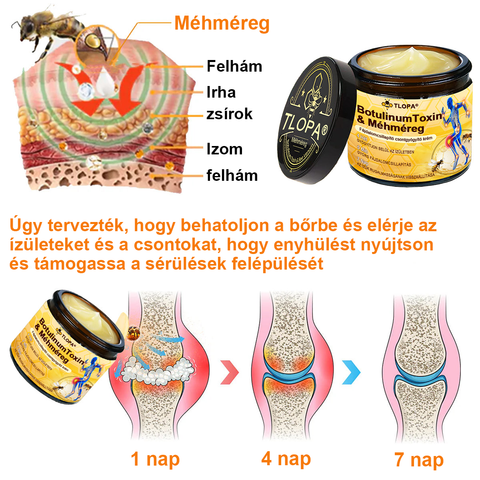

TLOPA® Botulinum Toxin és Méhméreg Fájdalomcsillapító Csontgyógyító Krém

a Magyar Ortopéd Társaság (MOT) által tanúsított és ajánlott termék, amely megfelel a magas szabványoknak a fájdalom hatékony enyhítésére és a csontok egészségének elősegítésére. Az ortopéd orvosok által jóváhagyott, 5 percen belül enyhíti a fájdalmat, 7 nap alatt visszaállítja az ízületi mozgékonyságot, és 4 héten belül jelentősen javítja az arthritis tüneteit. Válassza a Botulinum Toxin és Méhméreg Fájdalomcsillapító Csontgyógyító Krémet, és élvezze a megbízható eredményeket és a kellemes élményt bizalommal.

A TLOPA® Botulinum Toxin & Bee Venom Pain-Relief Bone Healing Cream segít az osteoarthritis, reumatoid arthritis, bursitis, tendinitis, csontritkulás, köszvény, carpalis alagútszindróma, ínszalag rándulások és húzódások, bütykök és teniszkönyök kezelésében.

A TLOPA® krém természetes méhméreg kivonatot tartalmaz, amely hatékonyan javítja az ízületek rugalmasságát. Az aktív összetevő, a "méhméreg peptid" mélyen behatol az ízületekbe, enyhítve a gyulladás okozta merevséget és kényelmetlenséget, segítve az ízületi mozgékonyság visszaállítását. Idővel a méhméreg gyulladáscsökkentő hatásai tovább serkentik a szinoviális folyadék termelését, jobb kenést biztosítva az ízületek számára, csökkentve a súrlódást, és jelentősen javítva az ízületi rugalmasságot 7 napon belül.

A botulinum toxin blokkolja a fájdalomjeleket, míg a méhméreg a bioaktív összetevői révén enyhíti a fájdalmat, így biztosítva a kettős fájdalomcsillapítást. Ezen kívül a méhméreg felgyorsítja a mikrokeringést és a sejtek regenerációját, együttműködve a botulinum toxin izomlazító hatásával, javítva az ízületek rugalmasságát és segítve az ízületi szövetek helyreállítását. Ez a kombináció nemcsak hatékonyan enyhíti az ízületi fájdalmat, hanem erősíti a csontokat, támogatja a hosszú távú csont-egészséget, és segít megelőzni az oszteoporózist és más csontdegeneratív problémákat.

A botulinum toxin egy erősen koncentrált oldat, amely gyorsan felszívódik a bőrön keresztül. Elengedhetetlen az izmok és ízületek egészségéhez, mivel segít az izmok ellazításában, enyhíti az izomgörcsöket, és csökkenti az arthritis által okozott fájdalmat. Emellett a botulinum toxin erős gyulladáscsökkentő tulajdonságokkal rendelkezik, amelyek segítenek csökkenteni az ízületek duzzanatait és gyulladását, javítva ezzel az ízületi mozgékonyságot.

A méhméreg számos aktív összetevőben gazdag, mint például a foszfolipáz A2, peptidek és enzimek, amelyek serkentik a vérkeringést és segítenek enyhíteni az arthritis és izomfájdalmat. A méhméreg természetes gyulladáscsökkentő tulajdonságokkal rendelkezik, csökkentve a gyulladási válaszokat, és enyhíti az ízületek duzzanatát és merevségét. Továbbá, a méhméreg elősegíti a szövetek regenerálódását, helyreállítja az ízületek mozgékonyságát, és javítja az általános mozgás képességét.